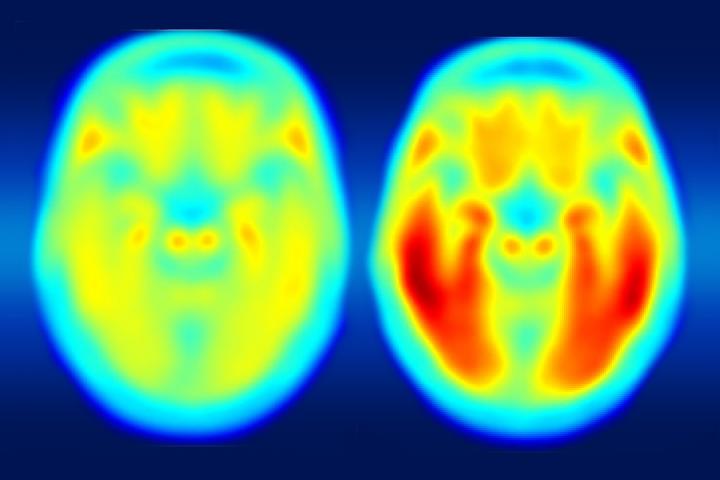

Using a new imaging agent that binds to tau protein and makes it visible in positron emission tomography (PET) scans, scientists at Washington University School of Medicine in St. Louis have shown that measures of tau are better markers of the cognitive decline characteristic of Alzheimer's than measures of amyloid beta seen in PET scans.

Comparing brain images of people who are cognitively normal to patients with mild Alzheimer's disease, the researchers found that measures of tau better predict symptoms of dementia than measures of amyloid beta. To determine degrees of cognitive impairment, some of the participants who underwent brain imaging also were assessed with the traditional clinical dementia rating (CDR) scale, cerebrospinal fluid measures, and widely used pen and paper tests of memory and other brain functions.

"The spinal fluid measures are very important, but they don't give us a complete spatial picture," he said. "Our new study suggests you can tolerate a certain amount of tau clumped in the hippocampus, but once it starts spreading into other areas, especially the lateral temporal and parietal lobes, that seems to be the tipping point."